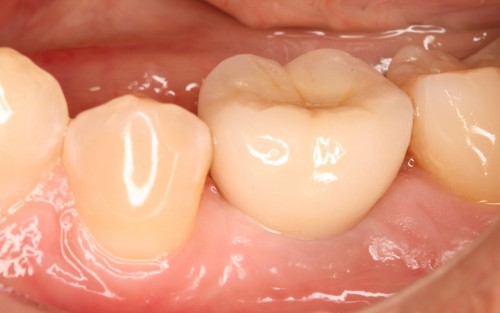

術前

インプラント挿入

土台装着

被せ物装着

同パノラマ写真

被せ物装着後歯肉の盛り上がり